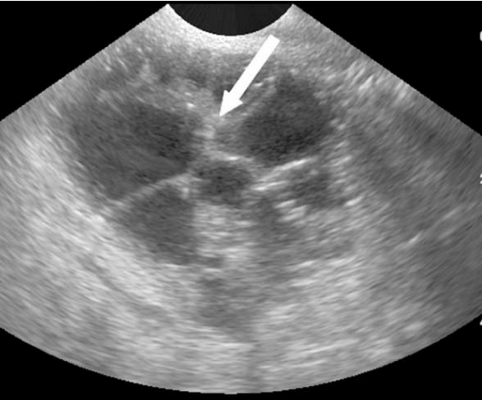

Рис.8. Метастазы рака мочевого пузыря: опухоль с размытыми краями, с гиперэхогенными перегородками различной ширины (стрелка).

Метастазы рака мочевого пузыря были обнаружены у трех (3,3%) пациентов. Размер опухоли колебался от 5 до 10 см. Все опухоли были интраперитонеальными, внутряичниковыми и односторонними с многокамерной структурой и гетерогенными перегородками. Количество камер было всегда меньше 10, ширина перегородок разная, с некротическими участками и размытыми краями (рис 8). Твердый компонент был некротическим с богатой периферической васкуляризацией.